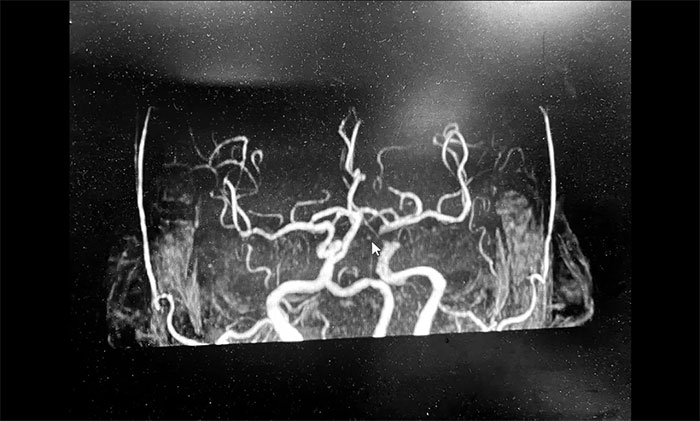

神經(jīng)內科3A病區(qū)周君主任詳細了解病史,查體,并為韓老伯完善相關的檢查。頭顱MRI示:腦干及雙側大腦半球多發(fā)陳舊梗死灶,左側胼胝體、半卵圓中心、側腦室旁及額葉多發(fā)梗死灶,偏亞急性期。腦動脈硬化,顱底動脈多發(fā)不同程度狹窄(左側頸內虹吸段為著)。

▲ 頭顱MRI示:左側多發(fā)梗死灶,左側頸內動脈狹窄

周君主任表示,從影像學上,患者左側腦室旁散在多個新鮮梗死灶,呈比較典型的“分水嶺樣梗塞”表現(xiàn)。分水嶺樣梗塞(Watershed infarction,WI),是指發(fā)生在腦部兩條主要動脈分布區(qū)的交界處的腦梗死,多發(fā)生于腦部較大動脈供血交界區(qū)。

韓老伯的新發(fā)病灶處在左側頸動脈供血支配范圍內,符合因左側頸內動脈狹窄而造成腦組織缺血表現(xiàn),需要針對這一引起腦梗的病因,及時采取干預治療措施。

周君主任立即與醫(yī)院學術副院長兼神經(jīng)內科4A病區(qū)主任席剛明教授,針對患者病情開展了討論評估,由席教授為患者行DSA全腦血管造影檢查,可見左頸內動脈眼動脈重度狹窄(狹窄程度約高于80%)。隨后,4A病區(qū)席剛明教授、王貴平博士為患者開展了左頸內動脈球囊擴張+支架置入手術,手術過程順利。